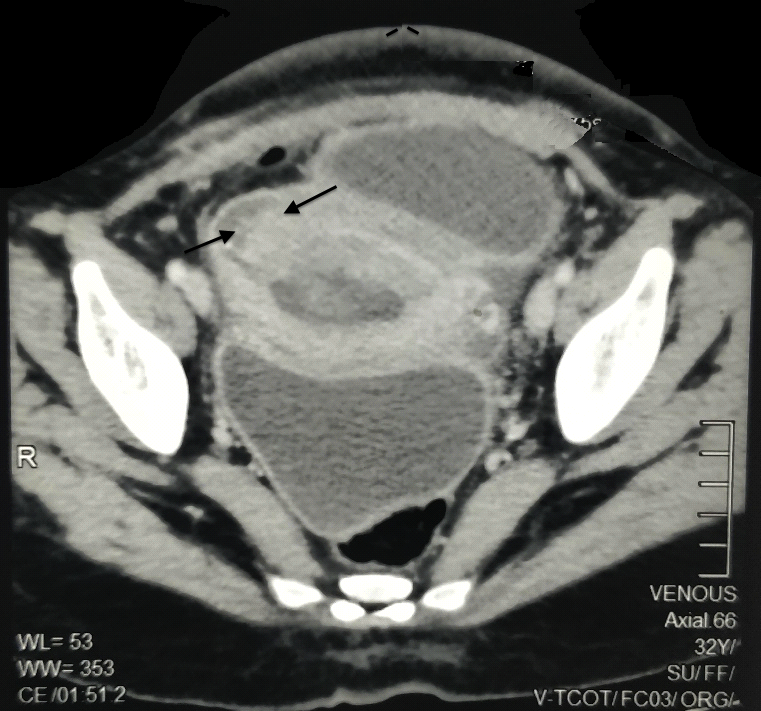

Uterine cesarean scar dehiscence Image Dehiscence Scar Tissue Dehiscence typically occurs within the first one to two weeks following surgery. Wound dehiscence describes a potential complication of surgery. Dehiscence is a partial or total separation of previously approximated wound edges, due to a failure of. Wound dehiscence is a surgery complication where the incision, a cut made during a surgical procedure, reopens. Poor blood flow to the. Wound. Dehiscence Scar Tissue.